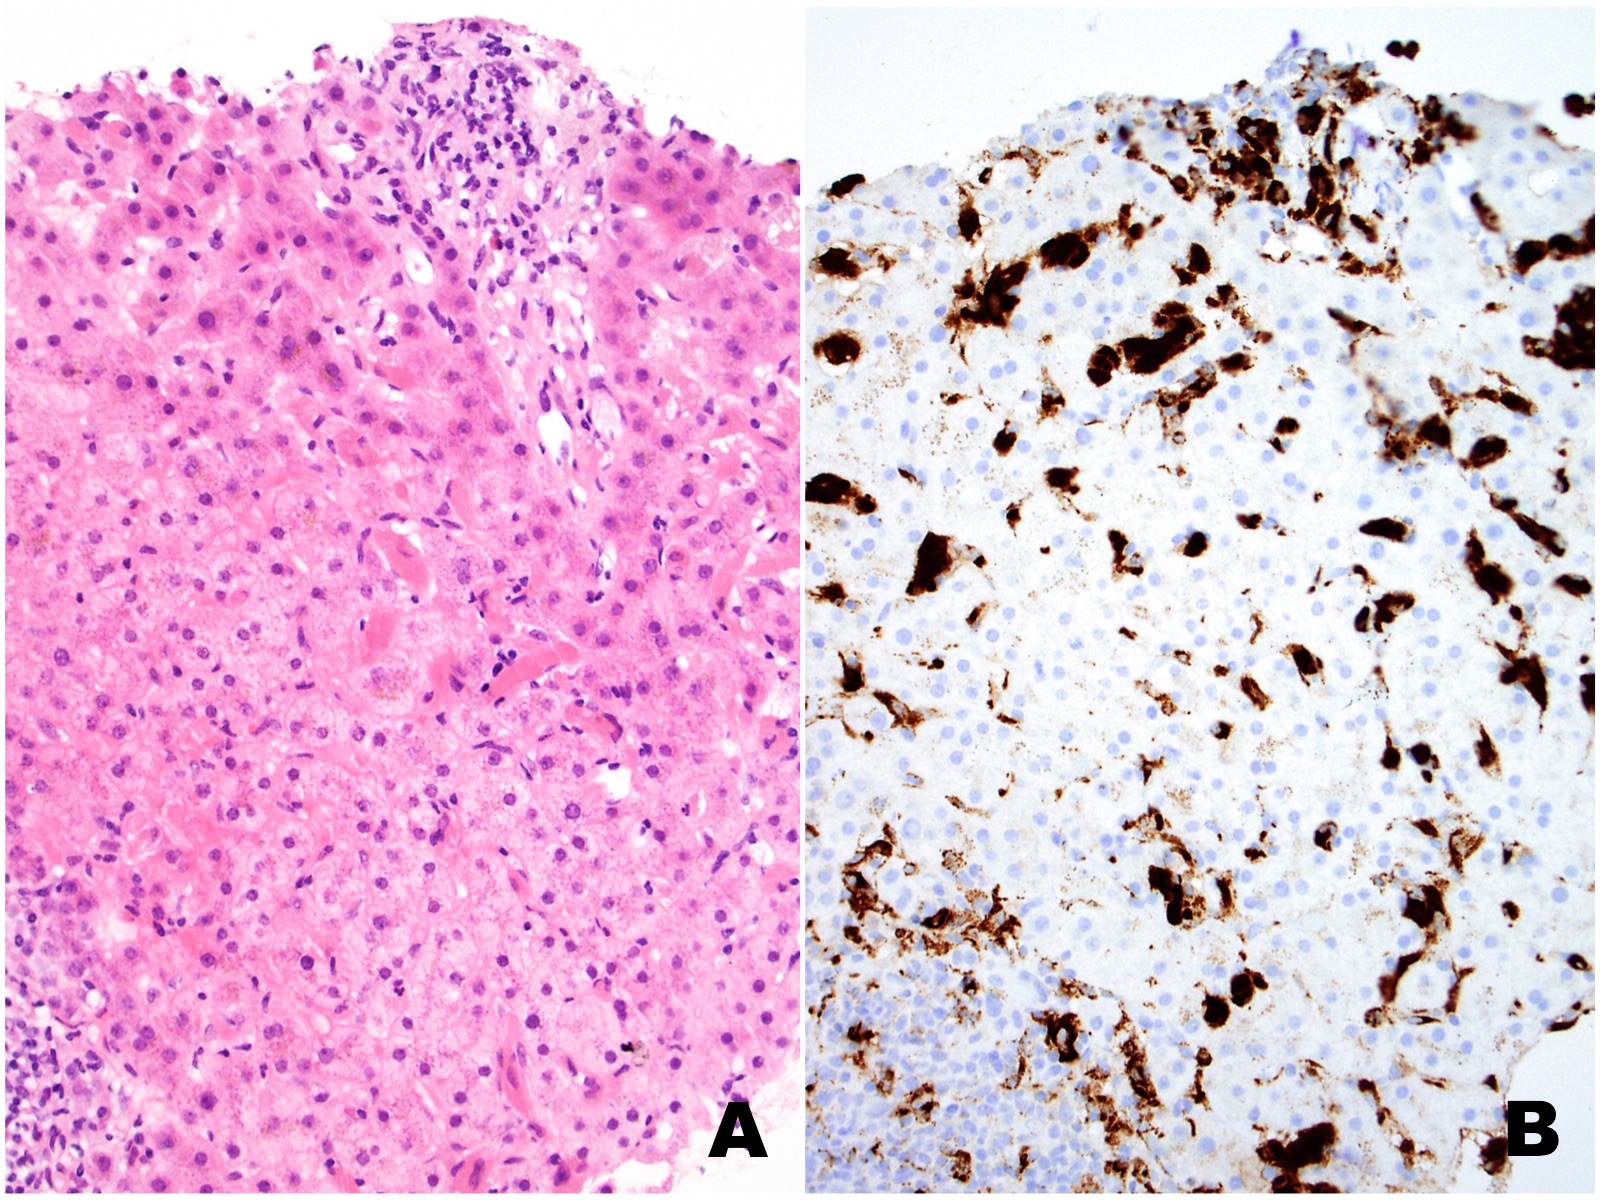

In a single portal tract there is mild inflammation associated with bile duct injury (Figure 4). One periportal area is positive for focal copper accumulation on the Rhodanine stain (Figures 5A and 5B, respectively). There were no histologic features of a concomitant clonal plasma cell or lymphoproliferative process.

This case is unusual in that there is focal bile duct injury with associated periportal copper accumulation. The very focal nature of these findings is insufficient for a diagnosis of primary biliary cirrhosis and the patient’s AMA is negative.